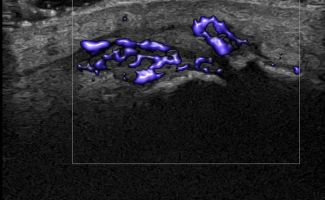

Hand Ultrasound examines joints, tendons, ligaments, nerves, and soft tissues of the hand. Pathologies that can be diagnosed by Hand Ultrasound are numerous, including:

Rheumatic Diseases

- Rheumatoid Arthritis

- Psoriatic Arthritis